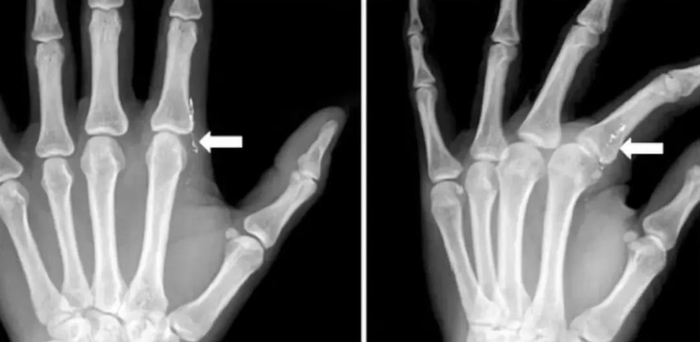

J Hand Surg Asian Pac 曾发表过这样一个病例:

一名 42 岁的妈妈去看病,觉得「左食指有异物感」。

医生追问病史了解到,她在 1 个月前在给女儿量体温时,不小心打碎水银温度计。清理体温计碎片的时候,左手指被刺伤,当时觉得没有大碍,就没有就诊。

医生发现,患者左手手指有肉芽组织,检验血液、尿液后发现,有汞中毒的迹象。

左食指第二掌指关节桡侧疼痛

图片来源:J Hand Surg Asian Pac Vol. 2017 Dec;22(4):519-522.

X 片可见皮下线状高密度影